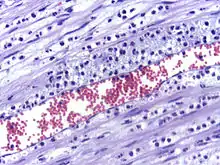

تسرب خلايا متعادلة من الوعاء الدموي إلى موقع الإصابة أو العدوى.

تسرب كريات الدم البيضاء عادة ما يحدث في الأوردة ما بعد الشعيرات الدموية حيث تكون إجهادات القص للدم ضئيلة نسبياً. وتجري عملية التسرب في عدة خطوات، ألا وهي الانجذاب الكيميائي، والالتصاق المتدحرج، والالتصاق المحكم، والانسلال.